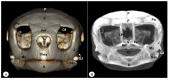

Anatomical Description of Loggerhead Turtle (Caretta caretta) and Green Iguana (Iguana iguana) Skull by Three-Dimensional Computed Tomography Reconstruction and Maximum Intensity Projection Images

The growing interest in reptiles has posed a challenge to veterinary clinicians due to the lack of a standardized system to perform anatomical studies similar to those used for dogs and cats. In this paper, we have attempted to describe, employing computed tomography and subsequent three-dimensional reconstructions, the normal anatomical features that comprise the skulls of two species of reptiles: the loggerhead turtle (Caretta caretta) and the green iguana (Iguana iguana). Computed tomography (CT) and subsequent image processing allowed the identification of the bony structures that comprise the head of these species. As a result, and based on previous articles, we propose the most significant anatomical differences and similarities between these species.